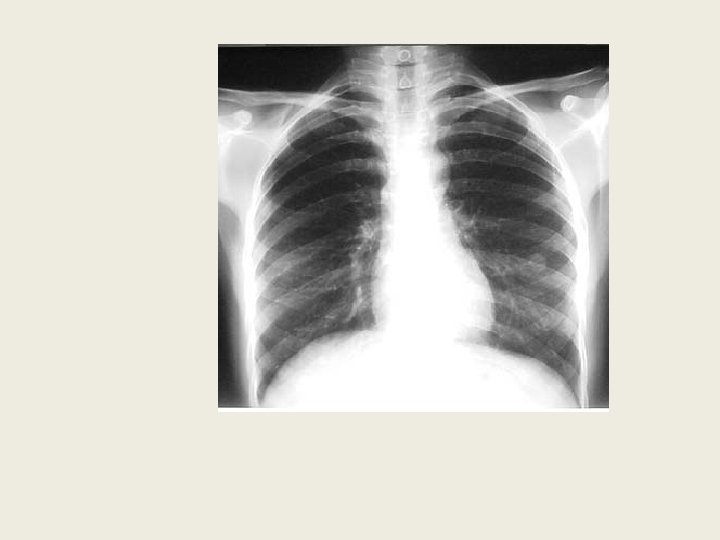

2. 1 Stade précoce(suite) • La radiographie pulmonaire montre : ü Nodules ü Infiltrats ü Cavernes Ø Atteinte préférentielle des lobes supérieurs des poumons